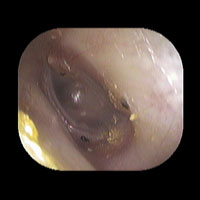

左急性中耳炎(重症)

鼓膜がやや赤くなって腫れています。鼓膜の奥に膿が透けて見えています。抗生剤の内服で鼓膜切開を行わずに22日目で治りました。

初診日

7日目

14日目

22日目